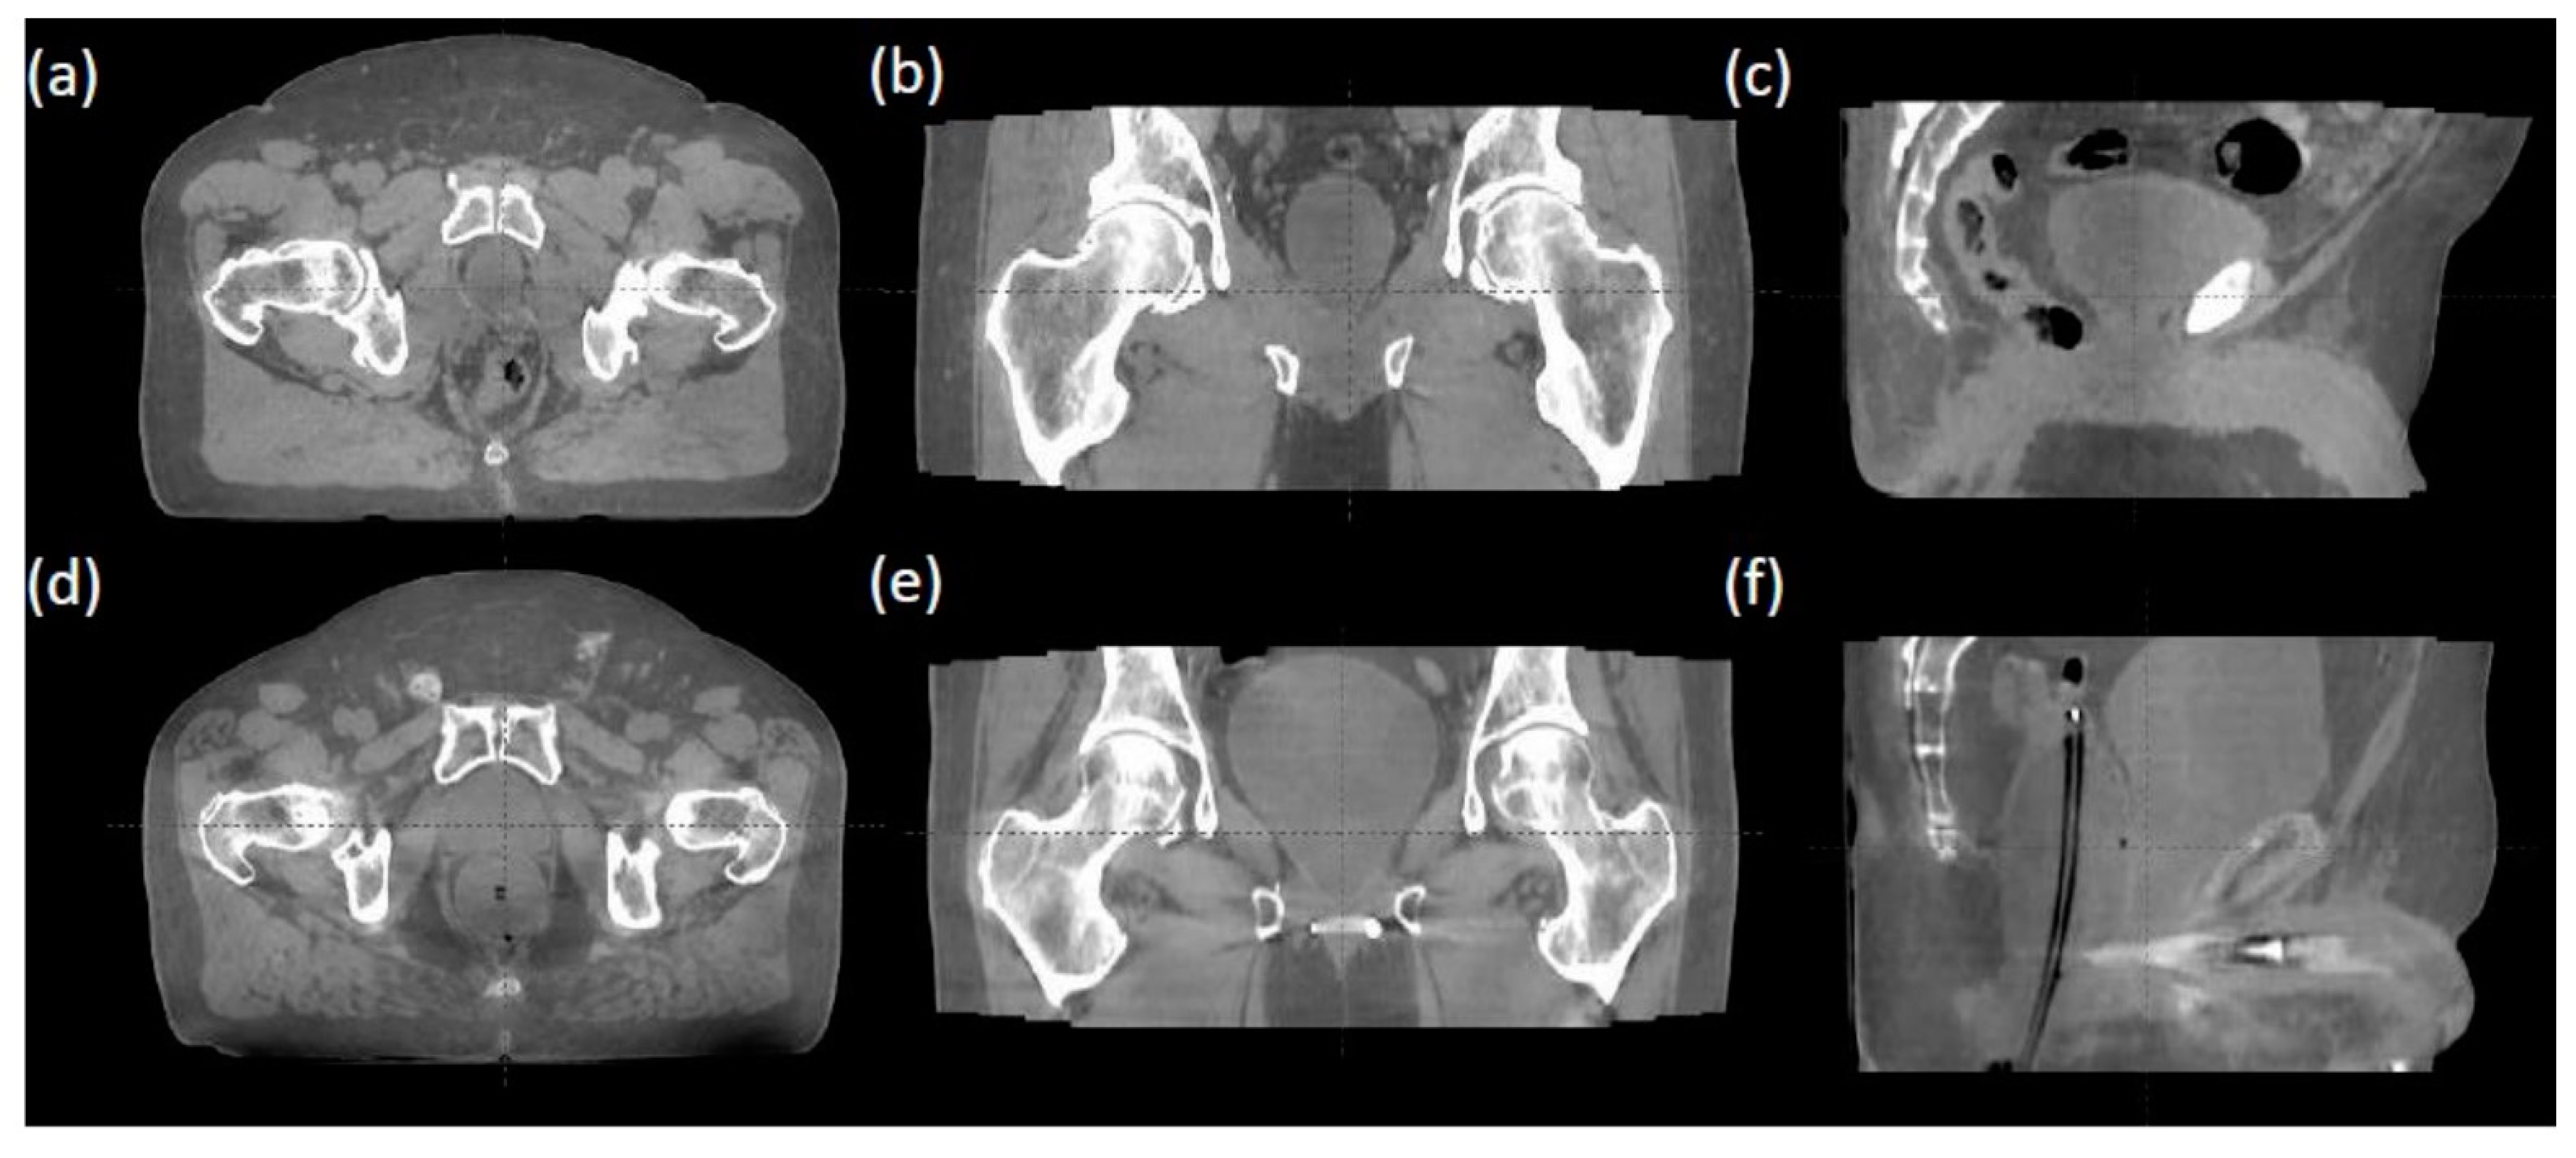

Each fraction’s iCBCT was taken prior to treatment for target localization using an On-Board Imager ® (Varian Medical Systems, Palo Alto, CA, USA) with a Pelvis Imaging mode setting (125 kVp, 1080 mAs, 900 projections, and 46.5 cm field of view) and Acuros CTS-based iterative reconstruction algorithm [21,22]. Upon confirming bladder filling by daily iCBCT, therapists then performed an automatic image registration between the planning CT and iCBCT with six degrees of freedom for couch turned on, followed by manual fine-tuning based on the rectum and bladder interfaces in axial, sagittal, and coronal views. Figure 1 provides an example of image registration accuracy using iCBCT compared to the planning CT. The rectal wall and bladder interface and the prostate bed from the obturator internus musculature in patients can be clearly differentiated on the iCBCT with and without an endorectal balloon. This soft tissue contrast quality allows therapists to accurately align the patient without seeing a solid target in a post-prostatectomy setting with clear IGRT matching instructions. Figure 2 demonstrates axial, coronal, and sagittal iCBCT reconstruction of a patient without endorectal balloon (Figure 2a–c) and with endorectal balloon (Figure 2d–f).

Figure 2.

(a–c) iCBCT reconstruction of a patient without endorectal balloon. (d–f) iCBCT reconstruction of a patient with endorectal balloon.